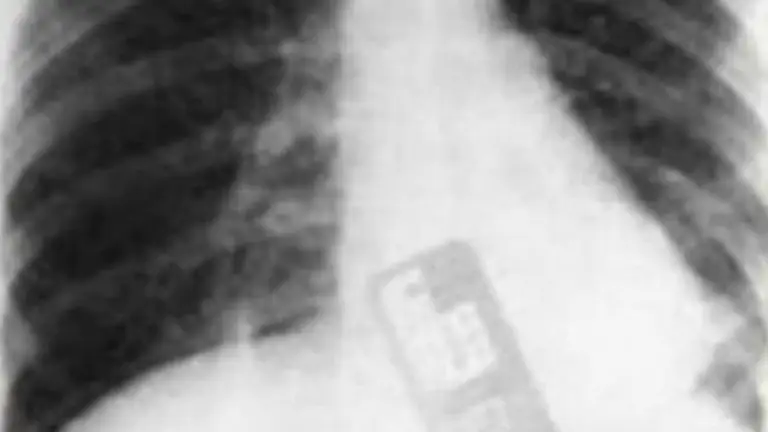

Una vez que le realizaron las imágenes correspondientes, se encontraron con una insólita respuesta: la mujer tenía un celular dentro de su cuerpo.